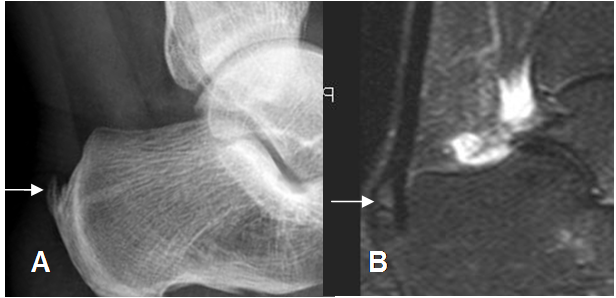

Fig 81. Tendinitis crónica del Aquiles.

A: Rx lateral. Calcificación sobre la inserción del tendón de Aquiles, por tendinitis crónica.

B: RM sagital en STIR. Calcificación en la inserción del Aquiles, con edema óseo por osteitis, pero se conserva la SI del tendón.